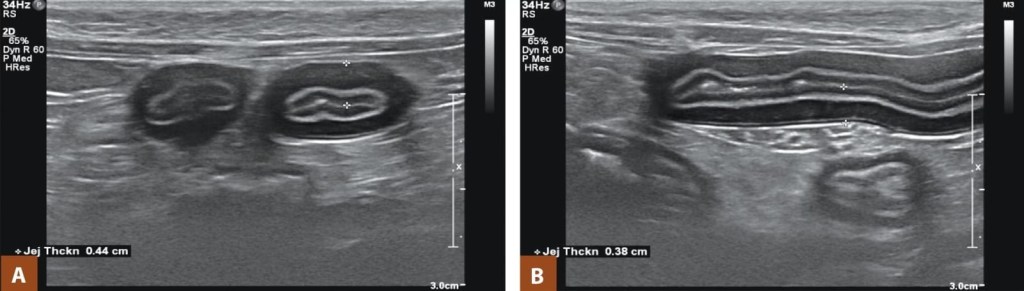

Şekil 2. İnflamatuvar bağırsak hastalığı (IBD) olan bir kedide jejunal kas tabakasının kalınlaşmasını gösteren ultrason görüntüleri: (A) Kalınlaşmış ince bağırsak duvarını gösteren enine kesit (0,44 cm). (B) Benzer şekilde kalınlaşmış görünüm (0,38 cm). Kedilerde normal ince bağırsak duvar kalınlığı 0,16–0,36 cm olarak bildirilmiştir (Garraway, Allenspach & Jergens, 2017). Dr. Jacob Ewing’in izniyle.